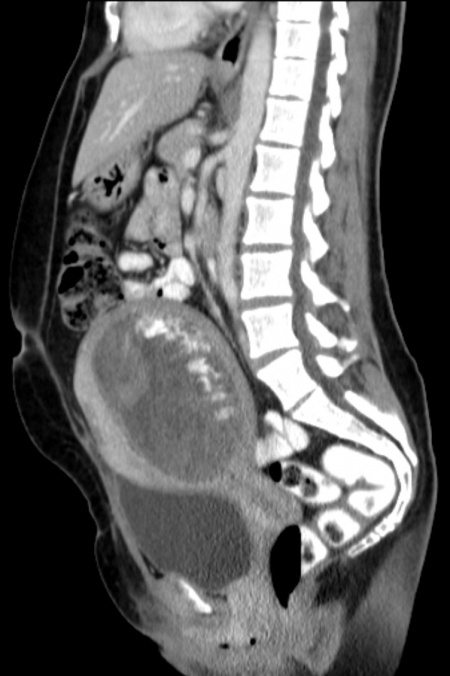

molar pregnancy differential diagnosis diagnosis at a glance: partial hydatidiform molar pregnancy

Diagnosis At A Glance: Partial Hydatidiform Molar Pregnancy | MDedge

Diagnosis at a Glance: Partial Hydatidiform Molar Pregnancy | MDedge www.mdedge.com

Diagnosis at a Glance: Partial Hydatidiform Molar Pregnancy | MDedge ...